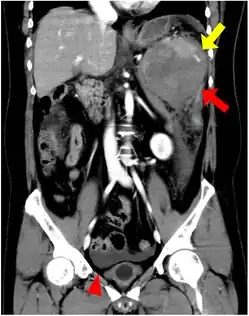

| CT scan of an accessory spleen (circular object in center of image) between the spleen and left kidney. | |

If splenectomy is performed for conditions in which blood cells are sequestered in the spleen, failure to remove accessory spleens may result in the failure of the condition to resolve.[1] During medical imaging, accessory spleens may be confused for enlarged lymph nodes or neoplastic growth in the tail of the pancreas,[5] gastrointestinal tract, adrenal glands or gonads.[2]